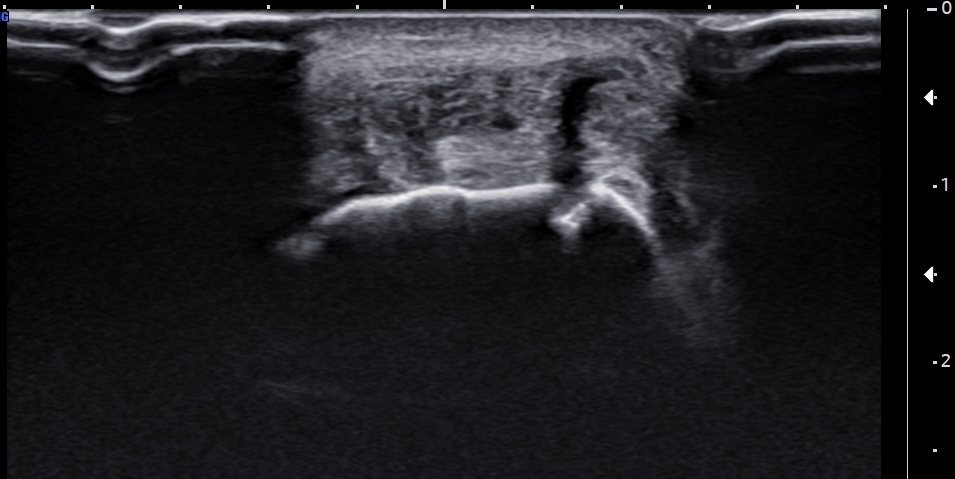

Unlabeled short-axis ultrasound image of the insertional Achilles tendon, a few millimeters distal to the superior edge of the calcaneus, demonstrating findings similar to those in Figure 4, with the addition of a clearly visible subcortical cyst.

Labeled short-axis ultrasound image of the insertional Achilles tendon, at the level of the superior edge of the calcaneus showing increased thickness, hypoechogenicity, and partial tearing of the deep tendon fibers.

Labels: AT: Achilles tendon, C: calcaneus, solid arrow: retrocalcaneal bursa, dashed arrow: partial tear.